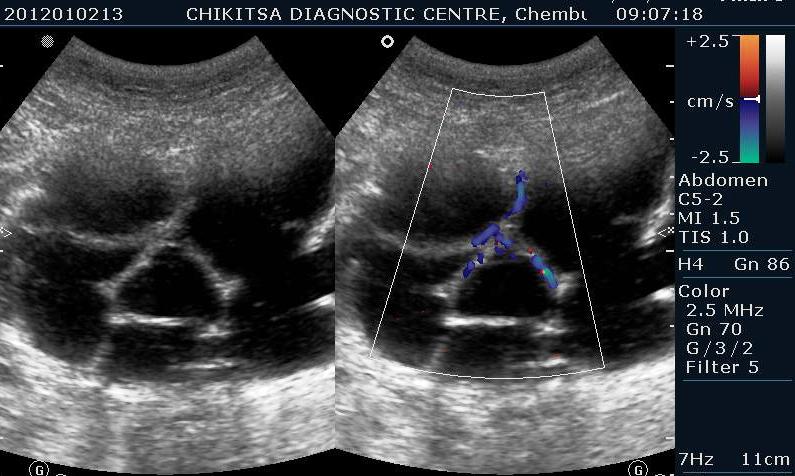

A 35 year old female was referred to our centre by a gynaecologist with gradually increasing distension abdomen & discomfort ,with pressure downwards. She had two alive children , both delivered normally & one early abortion , now tubectomised for 5 years.She had normal regular periods with cycle 3-5/25-35 days. No history of dysmenorrhoea.No history of any chronic medical illness. On ultrasound abdominally, one large mass of 15 cm x 10 cm with multiple septations was seen. On colour flow, vascularity was noted in the septal walls. No papillary projections seen in the mass.No solid areas seen in the mass.Uterus & right ovary were found to be normal. Diagnosis of left benign ovarian tumour ? mucinous cystadenoma was made which was confirmed on HPE after left ovariotomy .

Multiple thin septae are present and low levels echoes due to mucoid material present in the dependant portions of the mass. In mucinous Cystadenomas, individual locules may vary in imaging appearance due to difference in degree of hemorrhage and protein content. That's the differentiating point between serous and mucinous. Smooth inner wall structures are more reliable characteristics in predicting benignity. Presence of solid components and lesion without measurable wall thickness and demonstrable inner wall structure suggested malignancy. The difference in chemical components and difference in viscosity is responsible for sonographic echogenicity.

Identification of papillary projections on an imaging study is important because they are the single best predictor of the epithelial character of a neoplasm and may correlate with the aggressiveness of the tumor.